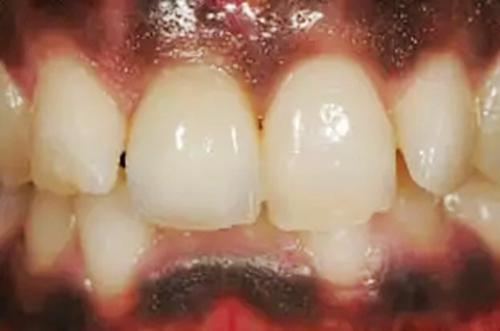

圖11、牙冠戴入1個(gè)月以后。軟組織外形良好,形成了良好的弧線形牙齦形態(tài)而沒有瘢痕。保持了原有的色素沉著的顏色和形狀。

圖12、種植術(shù)后1年顯示良好的美學(xué)效果。

圖14、最終修復(fù)體就位,冠頸部較窄。沒有任何牙齦和牙齦乳頭的退縮。

圖15、種植體植入后12個(gè)月的微笑相。